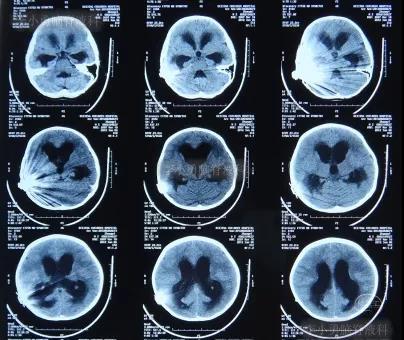

入院治疗18天即2012年6月25日,查脑CT示脑室有缩小(图-10)。

图-10:2012年6月25日脑CT

入院治疗55天即2012年8月1日,进行了脑室腹腔分流术,术后当天查脑CT示未见异常(图-11)。

图-11:2012年8月1日脑CT